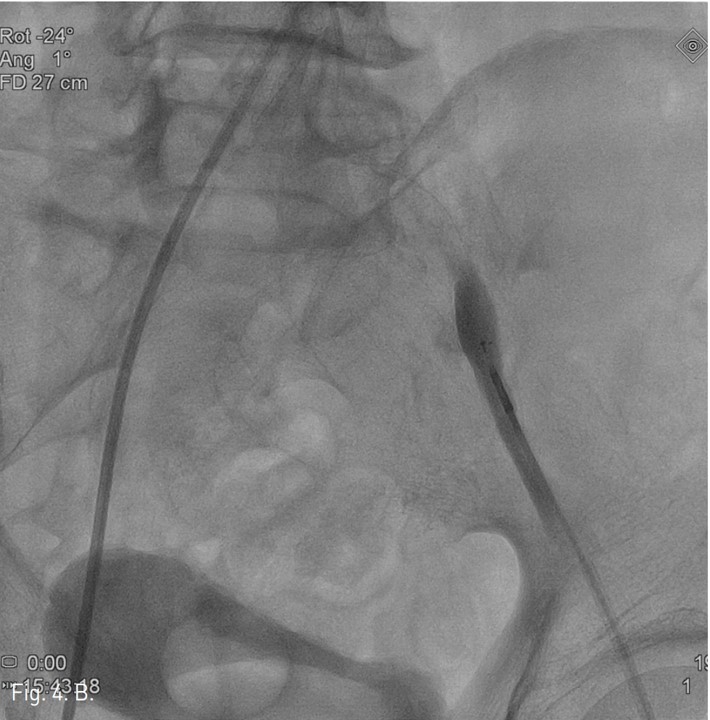

컴퓨터단층촬영 혈관조 영술과 고식적 혈관조영술에서 우측 총장골동맥에 석회화를 동반한 80%정도의 심한 협착이 있고, 좌측 총장골동맥에서 외장골동맥에 석회화를 동반한 완전 폐쇄의 소견이 있다 (Fig. 1A, IB). 우총대퇴동맥의 근위부에 10mm x 29mm Zenesis stent를 설치하였다 (Fig. 2). 0.035 inch guidewire로 좌측 총장골동맥의 기시부 폐쇄부위 통과를 시도하였으나 가성내강에서 진성내강으로 재진입이 되지 않았다 (Fig. 3). 좌측 외장골동맥 진성내강 내에 있는 ‘L-자’ 표시방향의 outback device가 보인다 (Fig. 4A), 좌측 외장골동맥 진성내강 내에 있는 'T-자’ 표시방향의 outback device가 보인다(Fig. 4B). Outback device를 이용하여 동맥내막을 천자후 0.014 inch guidewire를 가성내강 내로 진입시켰지만 좌측 총장골동맥-외장골동맥경 계부위에서 더 이상 진행되지 않았다 (Fig. 4C). 0.014 inch guidewire를 따라서 Davis catheter를 가성내강 내로 진입시키고 (Fig. 5A), 10mm snare를 삽입하여 Simmon catheter내부에 있던 microwire를 전진시켜 snare로 잡아 좌측 sheath로 뽑아내어 (Fig. 5B), 5Fr. Davis catheter를 대동맥 내부로 진입시켰다(Fig. 5C). 양측 총장골동맥 및 좌측 외장골동맥 스텐트 설치후 대동맥장골동맥조영술상에서 양측 장골동맥의 완전한 재개통을 보인다 (Fig. 6).

Fig. 4. B

B. Radiography taken while T-shaped marker of Outback device is seen.